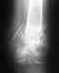

У меня патологические вывихи тазобедренних суставов,эту патологию дал сепсис который я перенесла при рождении.Мне 26 лет.С 7 месяцев лечилась в Свердловском НИИТО, оперировала меня Конферович Валерия Николаевна, а также Ирина Михайловна.В 1992г мне сделали аппарат Елизарова, после чего я хожу вот уже 16 лет.В 2006г. родила, правда было кесарево сечение.Врач ортопед не разрешил рожать самостоятельно т.к.у меня очень сильно ограничены движения.Теперь хочу сделать эндопратезирование в Саратовском НИИТО.Подскажите пожалуйста возможно ли у вас сделать такую опперацию? И Дорого ли это будет.А ещё на какой срок делаются протезы?

Для начала, вам нужно обратиться на очную консультацию в УНИИТО или в госпиталь ВВ на Широкой речке, со снимками после чего можно будет предметно обсуждать ваши вопросы. Консультативный прием в ГВВ: пн -12-15, птн-12-15, с собой иметь паспорт, полис, каб 535, поликлиника ГВВ.